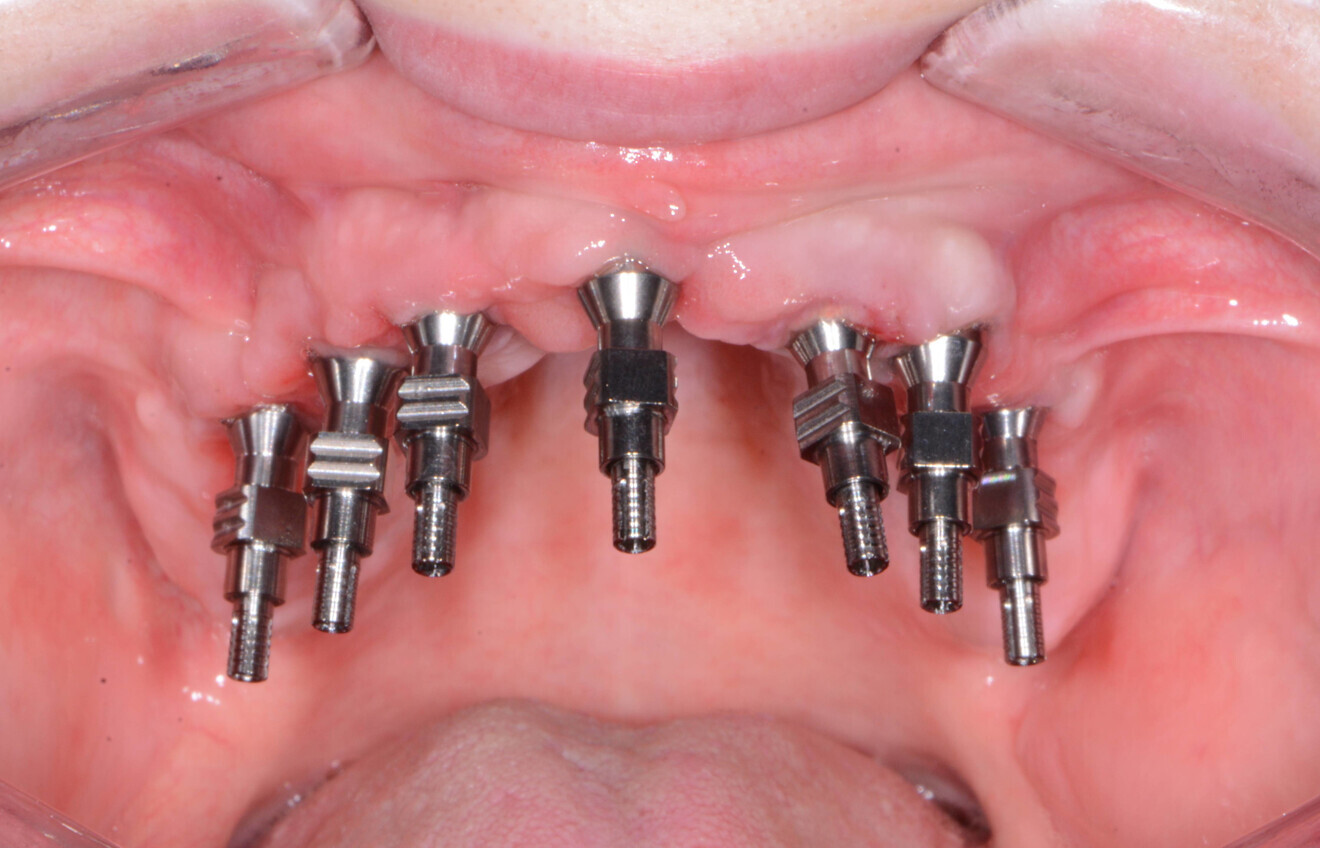

A baseline implant stability quotient (ISQ) reading was taken of these implants utilising the Penguin RFA unit (Aseptico). Since the initial readings were all above 72 ISQ and the quality of bone after levelling was good, transmucosal abutments (Adin Dental Implant Systems) were tightened into the Touareg-OS dental implants to 30 Ncm, followed by temporary cylinders to 15 Ncm.

Four months later, the patient presented for impressions for the definitive restoration. Using a heavy- and light-bodied polyvinylsiloxane material (Panasil, Kettenbach) in a stock tray, an open-tray impression was taken of the maxillary arch using transmucosal impression posts (Adin Dental Implant Systems; Figs. 13 & 14). From this impression, the dental laboratory fabricated a PMMA try-in of the proposed maxillary restoration for try-in and evaluation.

Fig. 13: Transmucosal impression posts.